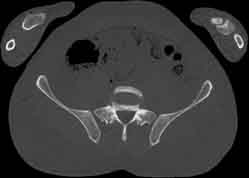

Visible Human male: Sectio transversalis 1769

CT

NMR

Pd                          / T2 \                         T1